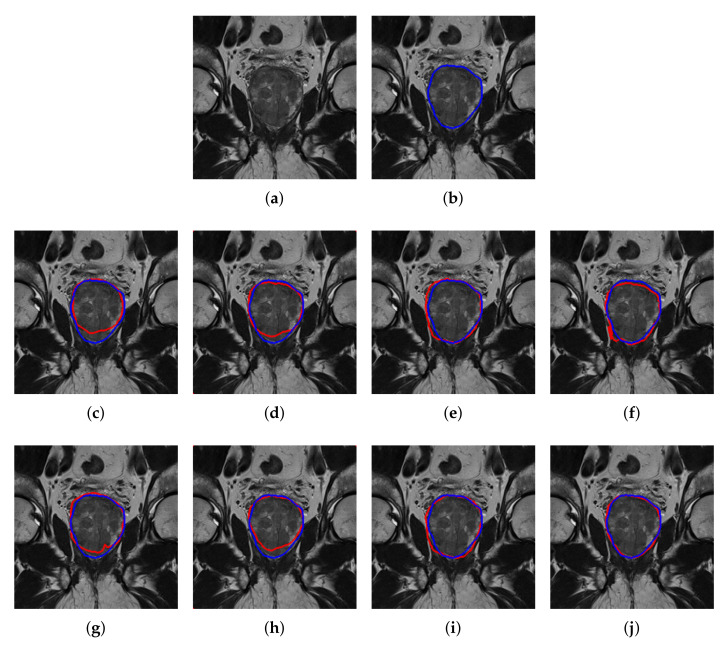

As for qualitative analysis, we present a sample of segmented images as shown in Figure 6 for both without and with the patch-wise method for PZ and CG regions. Visual comparison between without patch and with patch-wise indicates that more accurate segmentation can be achieved by patch-wise method. This highlights the significance of patch extraction which has enriched the CNNs with more data and improves its accuracy. It is notable from Figure 6 that the mask generated by the best CNN, DeepLabV3+ is closely similar in shape and size to the ground truth mask. In addition, DeepLabV3+ can accurately segment the region around the prostate boundary. On the other hand, FCN, SegNet, and U-Net are also able to segment prostate into PZ and CG regions but with less accurate segmentation, especially around the pixels close to the prostate boundary.

Figure 6.

Segmentation of prostate T2W MRI, from NCI-ISBI 2013 dataset into PZ and CG regions. (a) Original image, (b) ground truth boundary, where predicted boundary (red), overlay on the ground truth (blue), based on the method without patch extraction using, (c) FCN, (d) SegNet, (e) U-Net and (f) DeepLabV3+, and based on patch extraction using (g) FCN, (h) SegNet (i) U-Net and (j) DeepLabV3+.